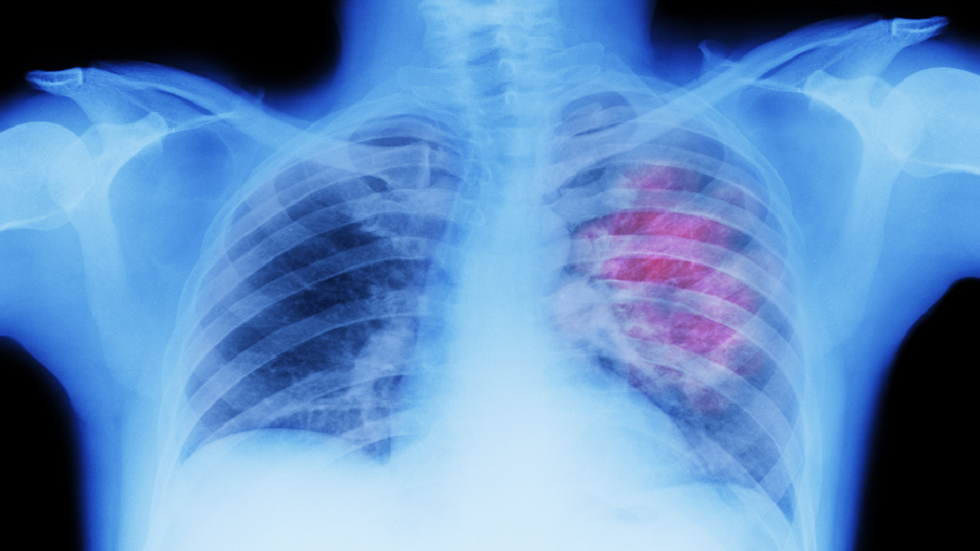

"مصاصة عملاقة تغذي السرطان".. مفتاح جديد لفهم علاقة التغذية بسرطان الرئة

بحثت دراسة جديدة، أجراها باحثون في جامعة فلوريدا للصحة بالتعاون مع مركز ماركي للسرطان بجامعة كنتاكي ومركز يو إف هيلث للسرطان، في تأثير النظام الغذائي على سرطان الرئة.

وركزت الدراسة على سرطان الرئة الغدي، الذي يمثل 40% من حالات سرطان الرئة عالميا. واستند البحث إلى دراسات سابقة حول مرض لافورا، وهو اضطراب عصبي نادر يتميز بتراكم الغليكوجين (شكل من أشكال تخزين الغلوكوز في الجسم) بمستويات عالية في الخلايا، ما يؤدي إلى تدهور عصبي سريع. وقد كشفت الدراسة أن الغليكوجين يعمل كمحفز لنمو الخلايا السرطانية في الرئة، وكأنه "مصاصة عملاقة تغذي رغبة السرطان في الحلويات".

وأظهرت التجارب أن ارتفاع مستويات الغليكوجين في الخلايا السرطانية يؤدي إلى زيادة حجم الأورام. وعندما خضعت الفئران لنظام غذائي غربي غني بالدهون والفركتوز – ما يرفع مستويات الغليكوجين في الدم – لوحظ نمو متسارع للأورام السرطانية في الرئة.

وعلى العكس، عندما انخفضت مستويات الغليكوجين، تباطأ نمو الأورام بشكل ملحوظ.

ويقول صن: "يعد الغليكوجين مؤشرا قويا لنمو الأورام السرطانية واحتمالية الوفاة لدى مرضى سرطان الرئة".